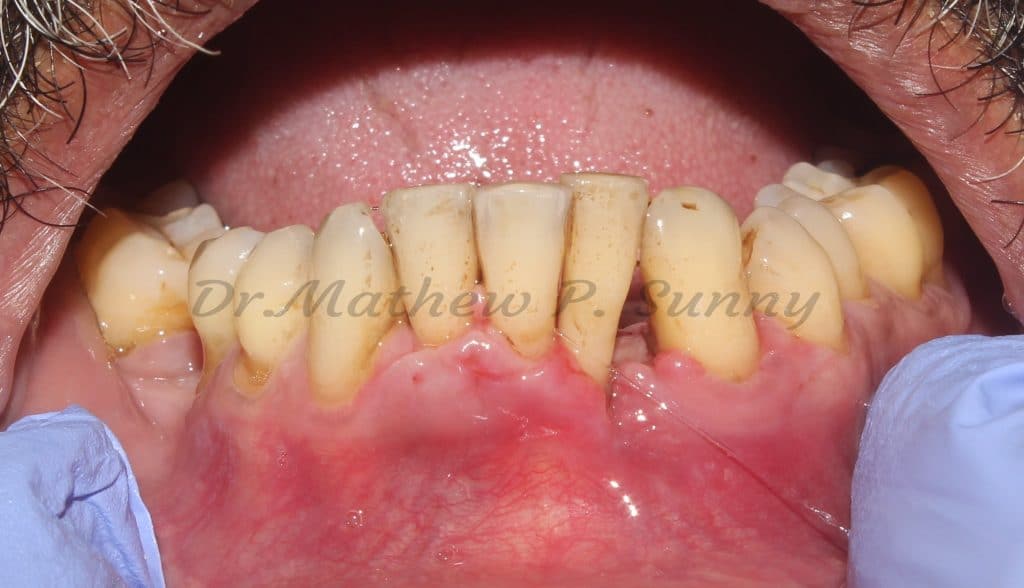

This patient presented with pain and swelling in relation to his lower left canine and lateral incisor.

Calculus was ++

Clinical presentation showing swelling in relations to the lower left canine and lateral incisor..